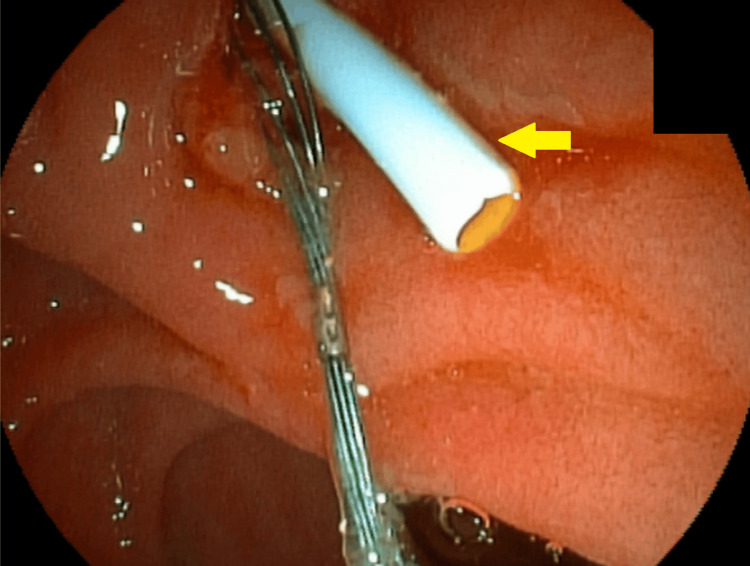

Mechanical lithotripsy was unsuccessful in fragmenting the stone, and a complication arose when the proximal rod of the basket broke, making it challenging to remove the basket along with the trapped stone (Figure 8).